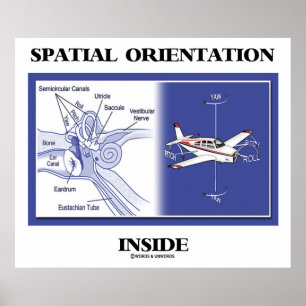

Poster Anatomia do ouvido humano

Preço159,00 €